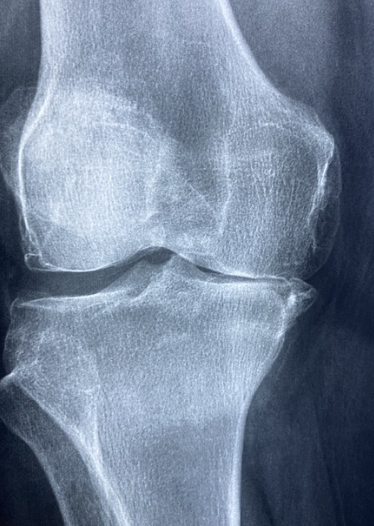

- 골관절염 : 골관절염은 관절염의 가장 흔한 형태이며, 일반적으로 관절의 노화 및 마모와 관련이 있습니다. 뼈 끝을 보호하는 보호 연골이 시간이 지남에 따라 마모될 때 발생합니다. 골관절염은 일반적으로 무릎, 엉덩이 및 척추와 같은 체중 부하 관절에 영향을 미칩니다. 증상으로는 관절 통증, 경직, 운동 범위 감소, 뼈 돌기 형성 등이 있습니다. 골관절염에 대한 치료법은 없지만 치료는 통증 관리, 물리치료, 생활 방식 수정 및 심한 경우 외과 개입에 중점을 둡니다.